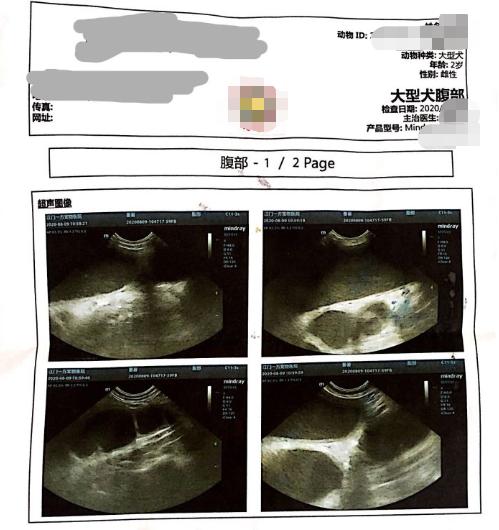

影像学诊断:因为胚胎45天内,在X光影像下并不明显,相对的,对于是否为怀孕或是子宫蓄脓就不容易早期诊断,此时腹腔超音波就有早期诊断的优势,因为胚胎成长24天后就可以藉由超音波来诊断,相对的,也可以更早区分怀孕(怀孕24天以后)与子宫蓄脓。